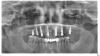

Wasja Опубликовано 29 декабря, 2012 Поделиться Опубликовано 29 декабря, 2012 Регистрация прикуса на трансферах, ФДМ. Ссылка на комментарий

Wasja Опубликовано 29 декабря, 2012 Поделиться Опубликовано 29 декабря, 2012 Контрольное орто, временные коронки на винтах установлены через 3 дня. Ссылка на комментарий